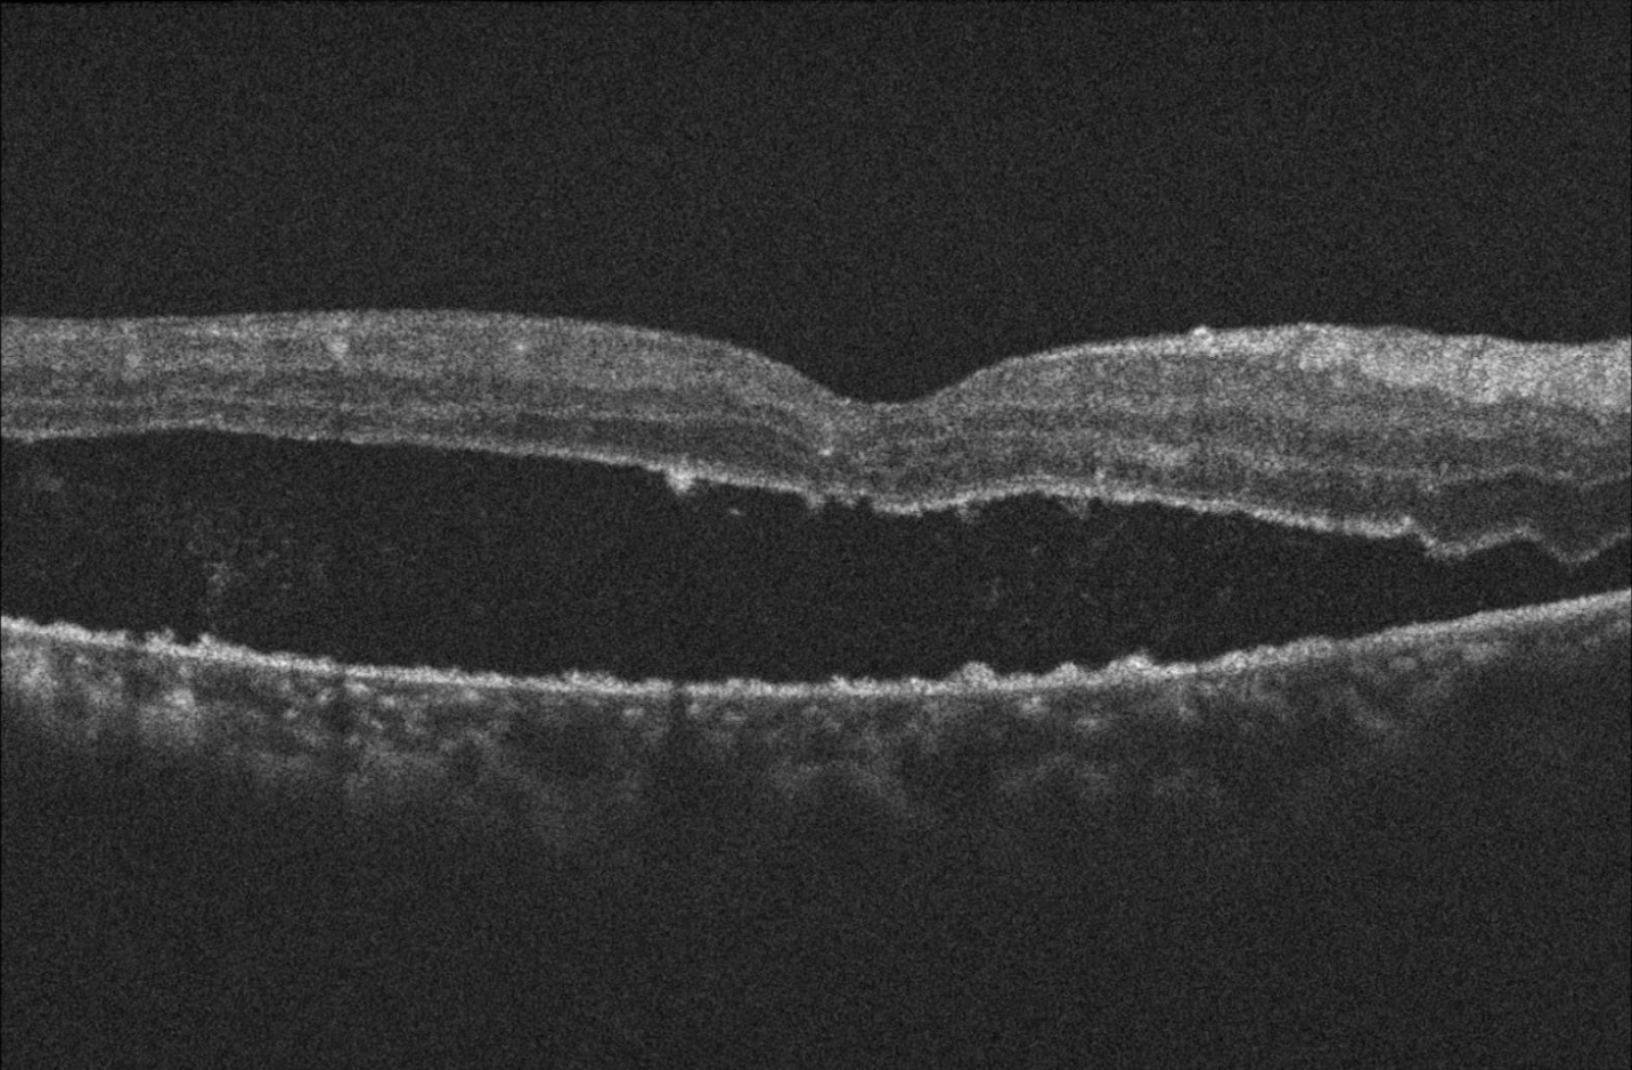

| Edema macular | ![]() | | ![]() | ![]() | Anti-VEGF Triamcinolona Dexametasona | Engrosamiento macular |

Disminución perfusión plexo superficial en OCTa